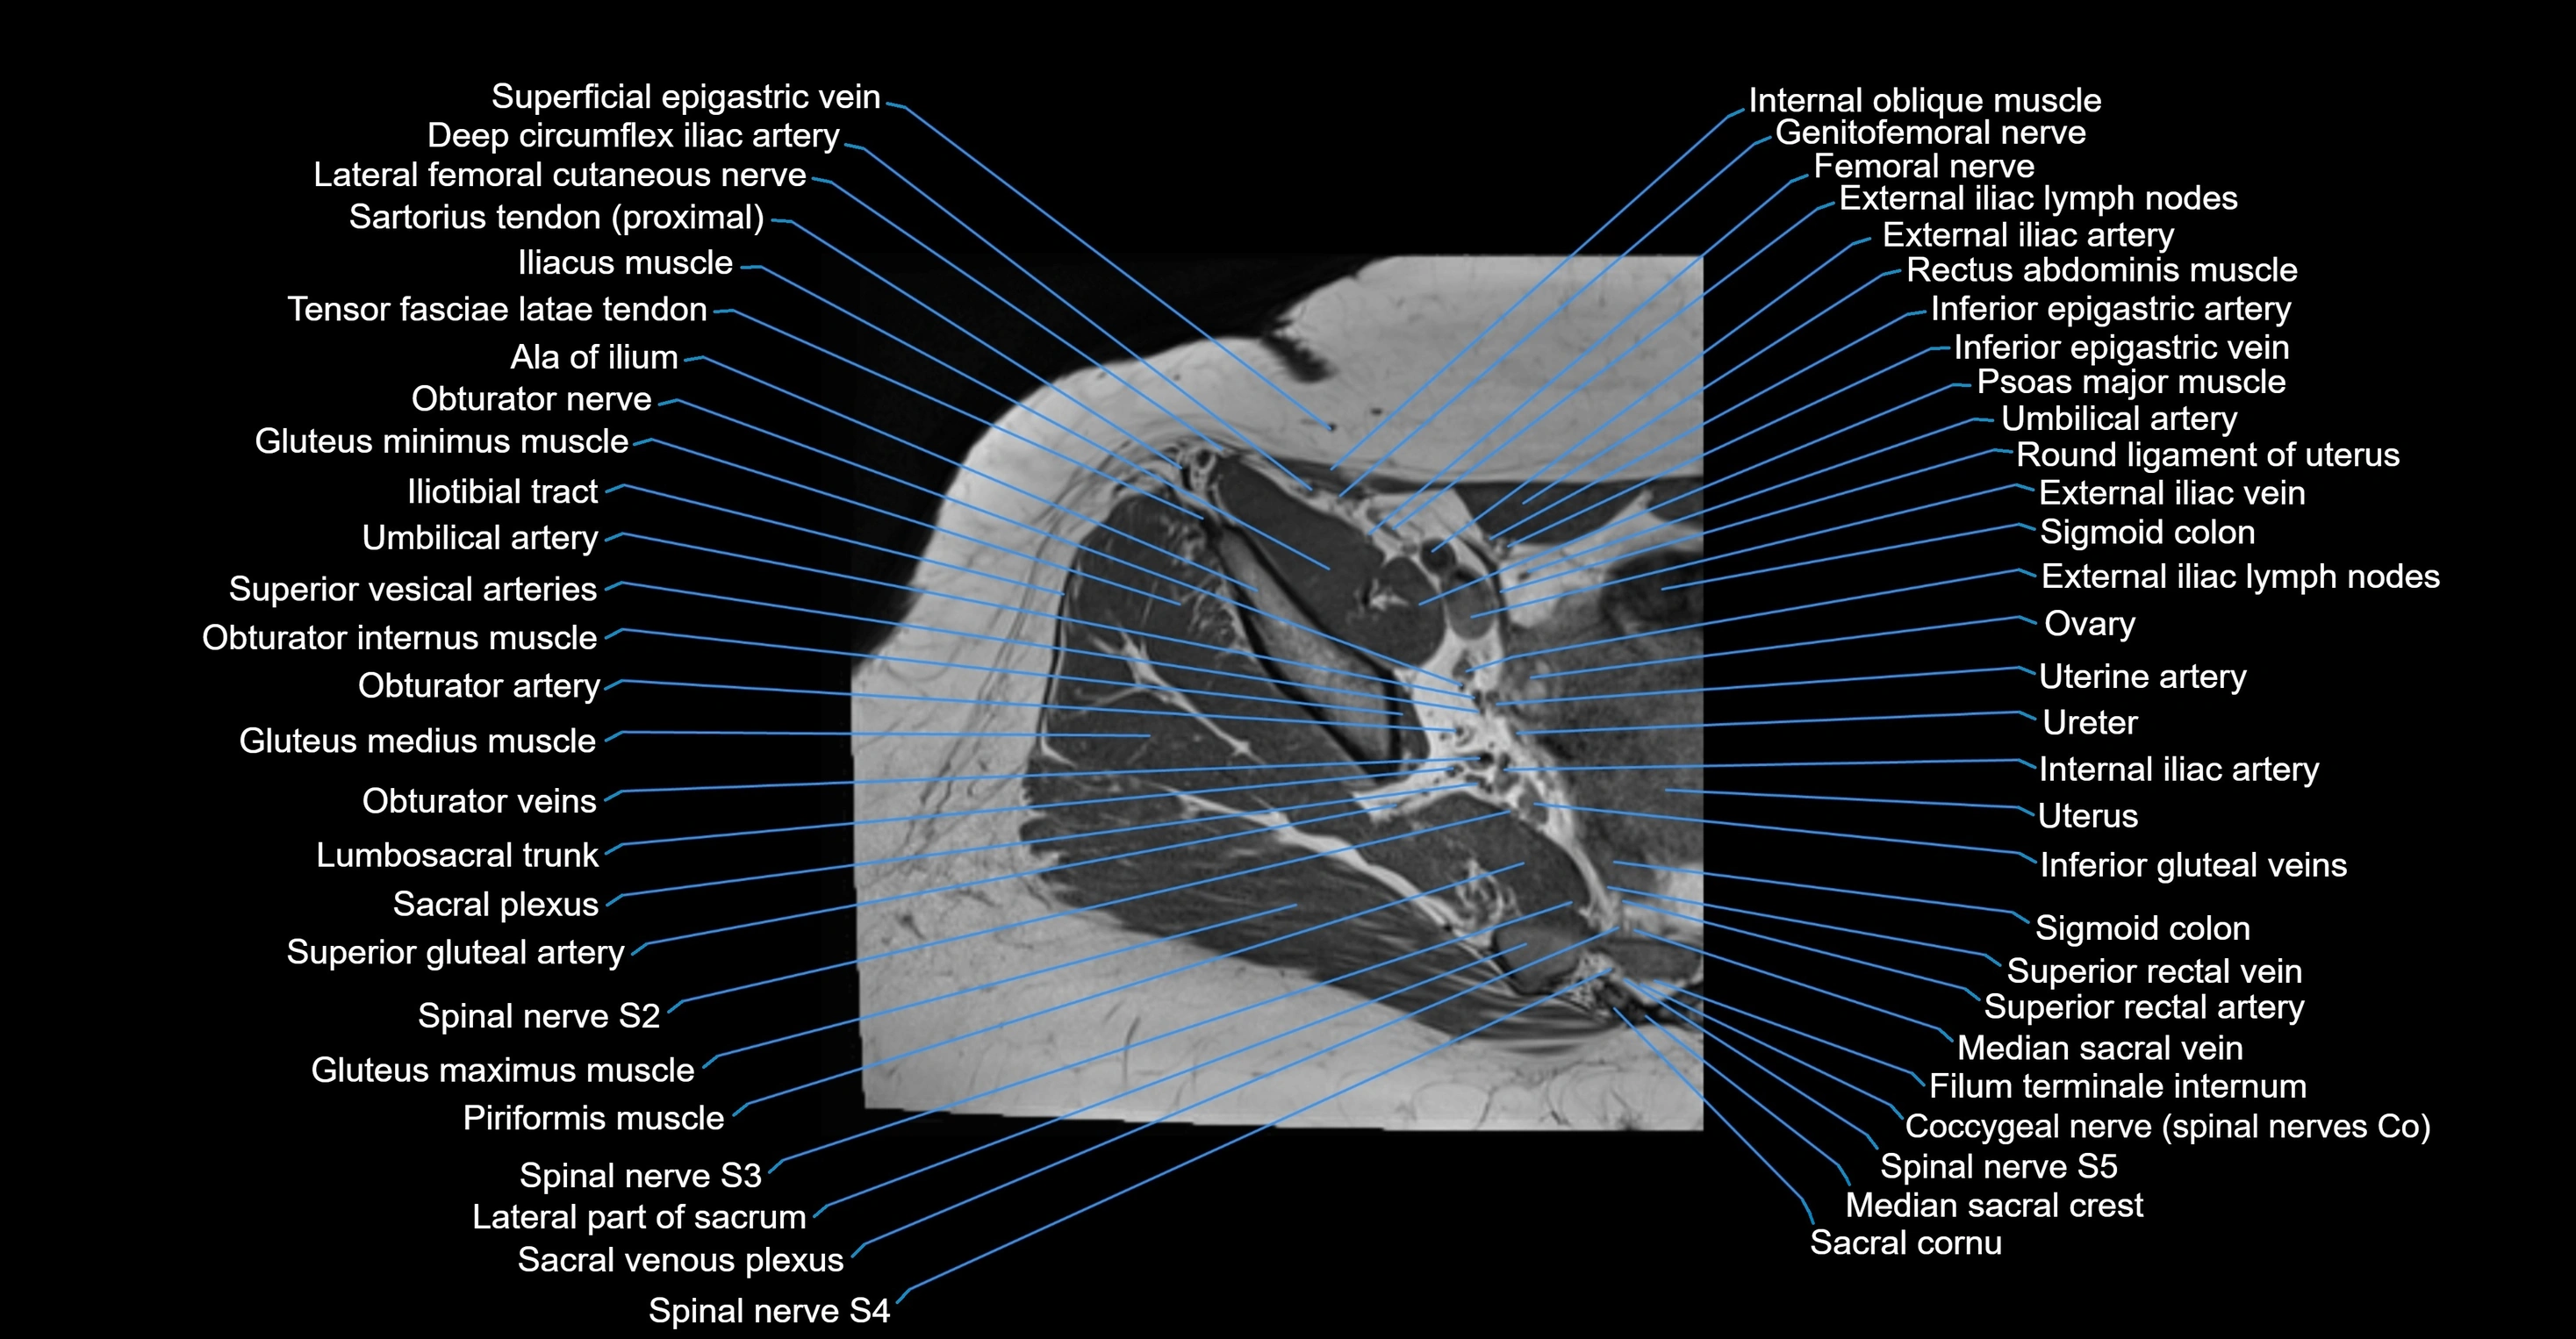

- Ala of ilium (wing of ilium)

- Deep circumflex iliac artery

- External iliac artery

- External iliac lymph nodes

- External iliac vein

- Femoral nerve

- Genitofemoral nerve

- Gluteus medius muscle

- Gluteus minimus muscle

- Iliotibial tract

- Ilium bone

- Internal iliac artery

- Lumbosacral trunk

- Median sacral vein

- Obturator artery

- Obturator internus muscle

- Obturator nerve

- Obturator vein

- Obturator veins

- Psoas major muscle

- Round ligament of uterus

- Sacral plexus

- Sacroiliac joint

- Sigmoid colon

- Spinal nerve S2

- Spinal nerve S3

- Spinal nerve S4

- Spinal nerve S5

- Superior gluteal artery

- Superior rectal vein

- Superior vesical artery

- Umbilical artery

- Uterine artery

- Uterus